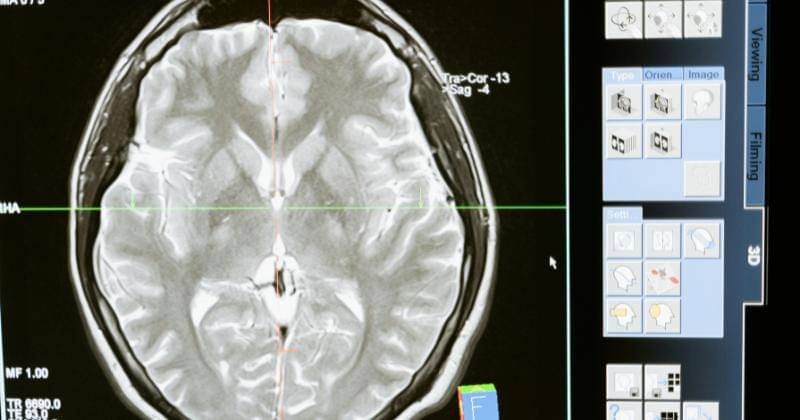

Neuralink, perusahaan neuroteknologi milik Elon Musk, telah mencapai tonggak sejarah dengan berhasil menanam chip di otak manusia untuk kedua kalinya. Peristiwa ini menandai langkah besar dalam pengembangan teknologi antarmuka otak-komputer yang berpotensi revolusioner.

Neuralink telah berhasil menanam chip pada otak pasien keduanya. Elon Musk mengumumkan keberhasilan ini dalam sebuah podcast bersama Lex Fridman. Meskipun tanggal pasti operasi tidak diungkapkan, Musk menyatakan bahwa implantasi berjalan dengan sangat baik.

Dari 1.024 elektroda yang ditanam, sekitar 400 elektroda dilaporkan berfungsi dengan baik. Hal ini menunjukkan kemajuan signifikan dalam teknologi implantasi otak Neuralink.